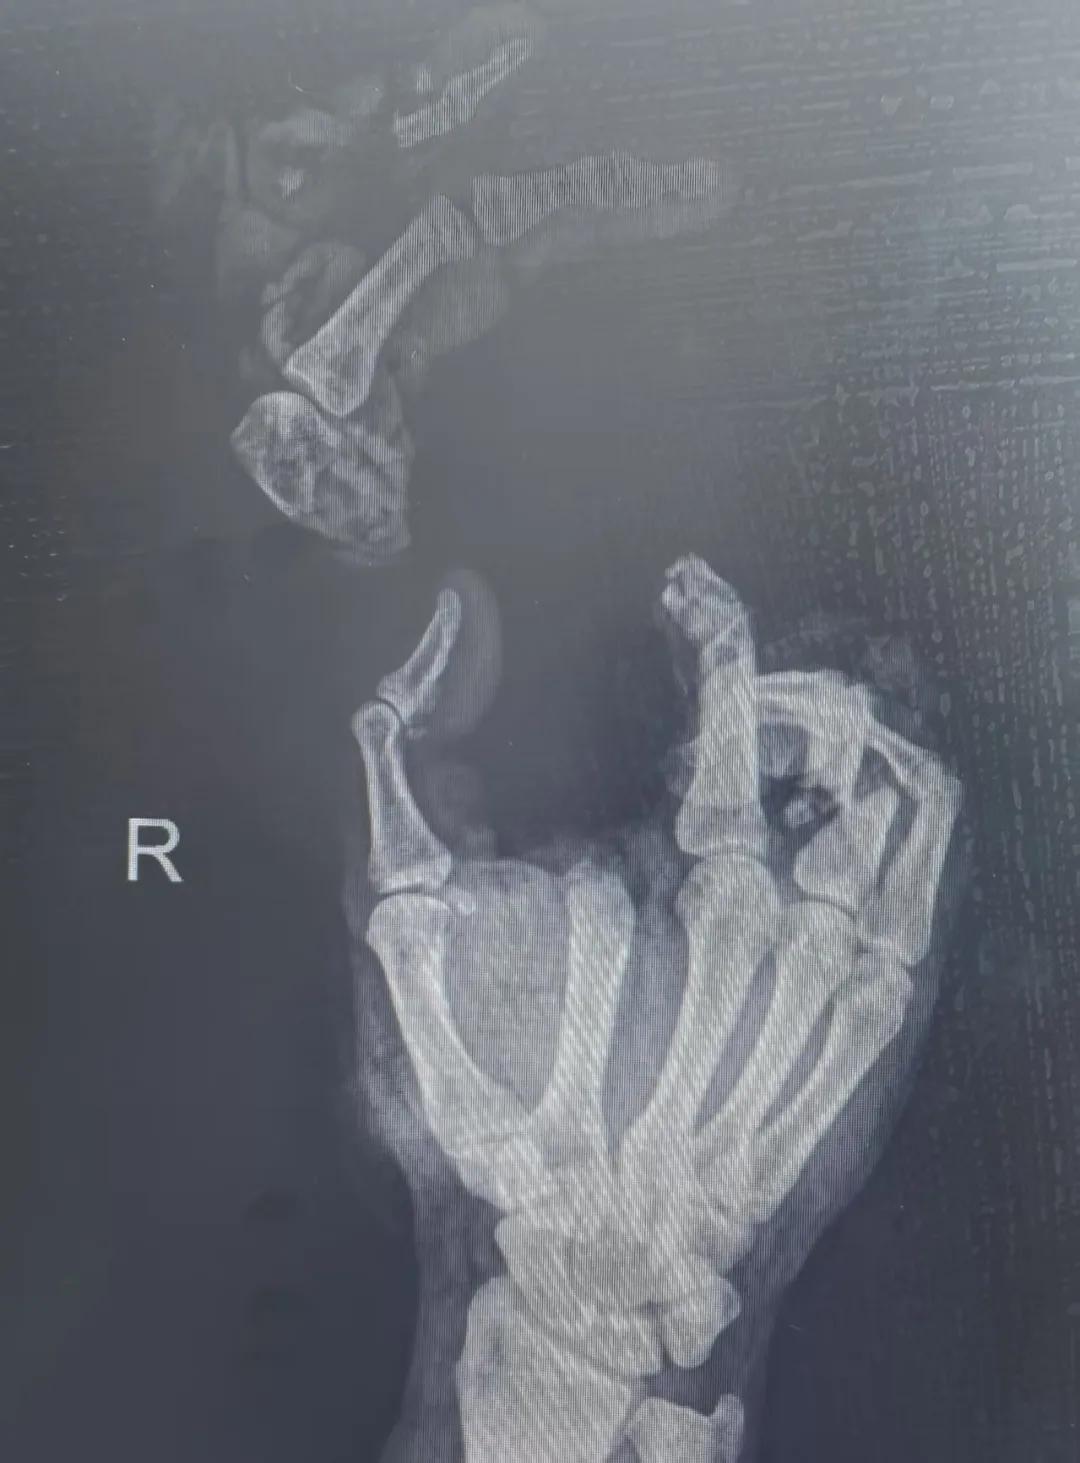

5月20日,市二院顯微外科燒傷整形科收治了3例因麥?zhǔn)毡晦r(nóng)機(jī)“咬傷”、農(nóng)具劃傷的患者。其中,56歲的劉某在收麥子時被打谷機(jī)皮帶絞傷右手,致手掌、食指、中指、環(huán)指嚴(yán)重毀損傷,骨、關(guān)節(jié)外露,因當(dāng)?shù)蒯t(yī)院無法治療,被家人緊急送往市二院顯微手足燒傷整形外科救治。“當(dāng)時整個右手血肉模糊,看上去都是爛的,我以為這個手是肯定保不住了。”患者家屬回憶當(dāng)時的場景仍然膽戰(zhàn)心驚。

患者入院后,經(jīng)X線檢查及創(chuàng)面檢查,醫(yī)生診斷為右手食指、中指及環(huán)指旋轉(zhuǎn)撕脫性離斷。接診的顯微手足燒傷整形外科醫(yī)護(hù)人員立即完善了各項術(shù)前準(zhǔn)備,并安排急診手術(shù)。因創(chuàng)面污染嚴(yán)重以及離斷肢體損傷程度較重,手術(shù)歷時近10小時。在沈衛(wèi)軍主任的帶領(lǐng)下,科室團(tuán)隊成功為其進(jìn)行了創(chuàng)面擴(kuò)創(chuàng)、斷肢再植術(shù),術(shù)后患指血運(yùn)良好,在進(jìn)一步觀察治療中。